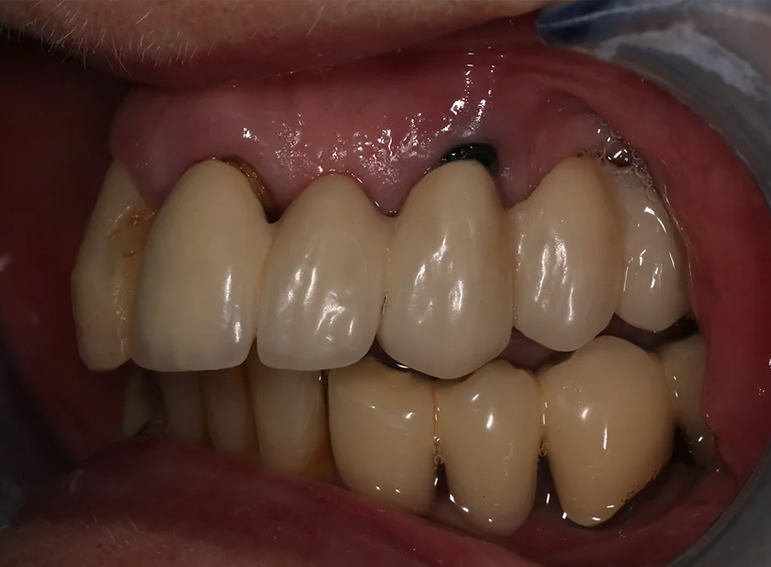

Case 17 – Prosthodontics

Extraction of failed bridge and temporary denture.